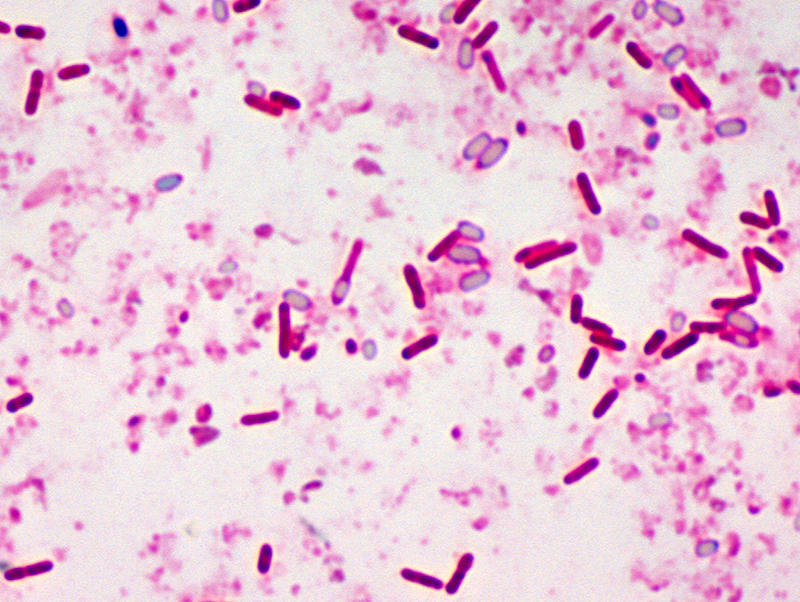

Botulism is a rare and potentially fatal illness caused by a toxin produced by the bacterium Clostridium botulinum and sometimes Clostridium butyricum and Clostridium baratii.

The bacteria that make botulinum toxin are common both in soil and water. They produce the botulinum toxin when exposed to low oxygen levels and certain temperatures.

♦ Spores

These bacteria make spores, which act like protective coatings. Spores help the bacteria survive in the environment, even in extreme conditions. The spores usually do not cause people to become sick, even when they are eaten. But under certain conditions, these spores can grow and make one of the most lethal toxins known.